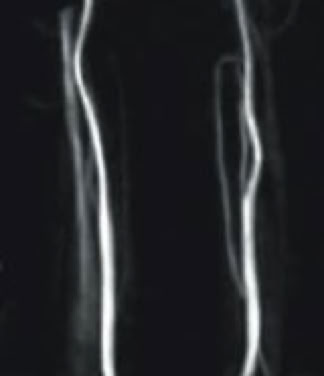

4. 頚動脈MRA:同様にMRIによる頚動脈の撮影です.頚動脈の狭窄,閉塞などを診断します.

頸動脈MRA

・頭部MRA,頚動脈MRA